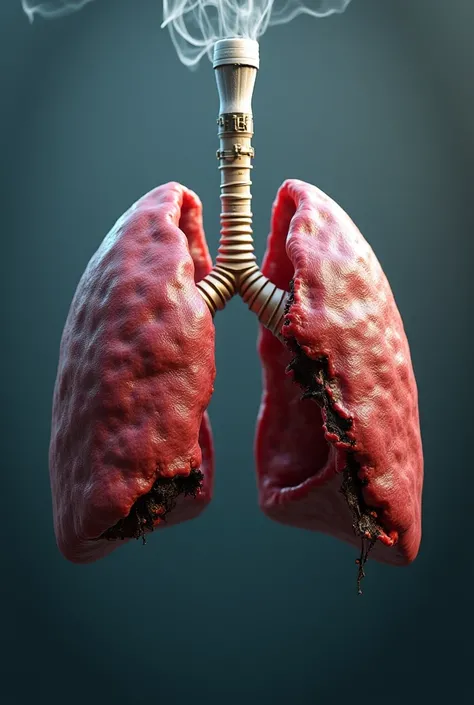

Generate a lungs, the right side lungs is healthy vibrant color surrounded with

Generate a lungs, the right side lungs is healthy vibrant color surrounded with fresh air. On the left side make the lungs damage or pollution of elements in smoking. Add some symbols of no smoking in the pulution part, and add some clean air in the right side lungs

On the left side make the lungs damage or pollution of elements in smoking